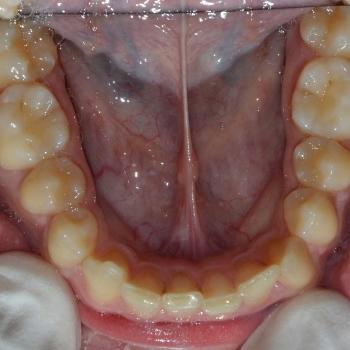

Ádám és édesanyja fogorvosuk javaslatára kerestek fel a felső állcsontban rekedt maradó szemfogak sorbaállításának kérésével. A panoráma röntgenfelvétel elemzése alapján egyértelművé vált, hogy a maradó szemfogak hibás tengelyállása okozta a tej szemfogak perzisztenciáját és a maradó szemfogak előtörésének a hiányát. A szemfogak 30 és 45 fokos dőlésének klinikai képet tovább árnyalták egyéb fogszabályozási eltérések is, mint például a mélyharapás, a nagymetszők közötti rés, illetve jobb oldali második nagyőrlők közötti fordított keresztharapás.

A probléma súlyosságát figyelembe véve, Ádám nagyon bölcsen az önligírozó fém fogszabályozó mellett döntött, melyet bite turbo harapásemelővel és különböző intermaxilláris gumihúzásokkal egészítettünk ki. Az önligírozó fogszabályozó ellenére a kezelés ideje igen hosszú volt. Ennek oka, hogy a szemfogak szájsebészeti feltárása közben derült fény a levontatantó fogak dőlésén kívüli 100-160 fokos tengely körüli elcsavarodására is.

Ádám kitartásának köszönhetően a kezelés végére minden maradó fog a helyére került és egy esztétikailag és funkcionálisan is tökéletes harapást kaptunk.